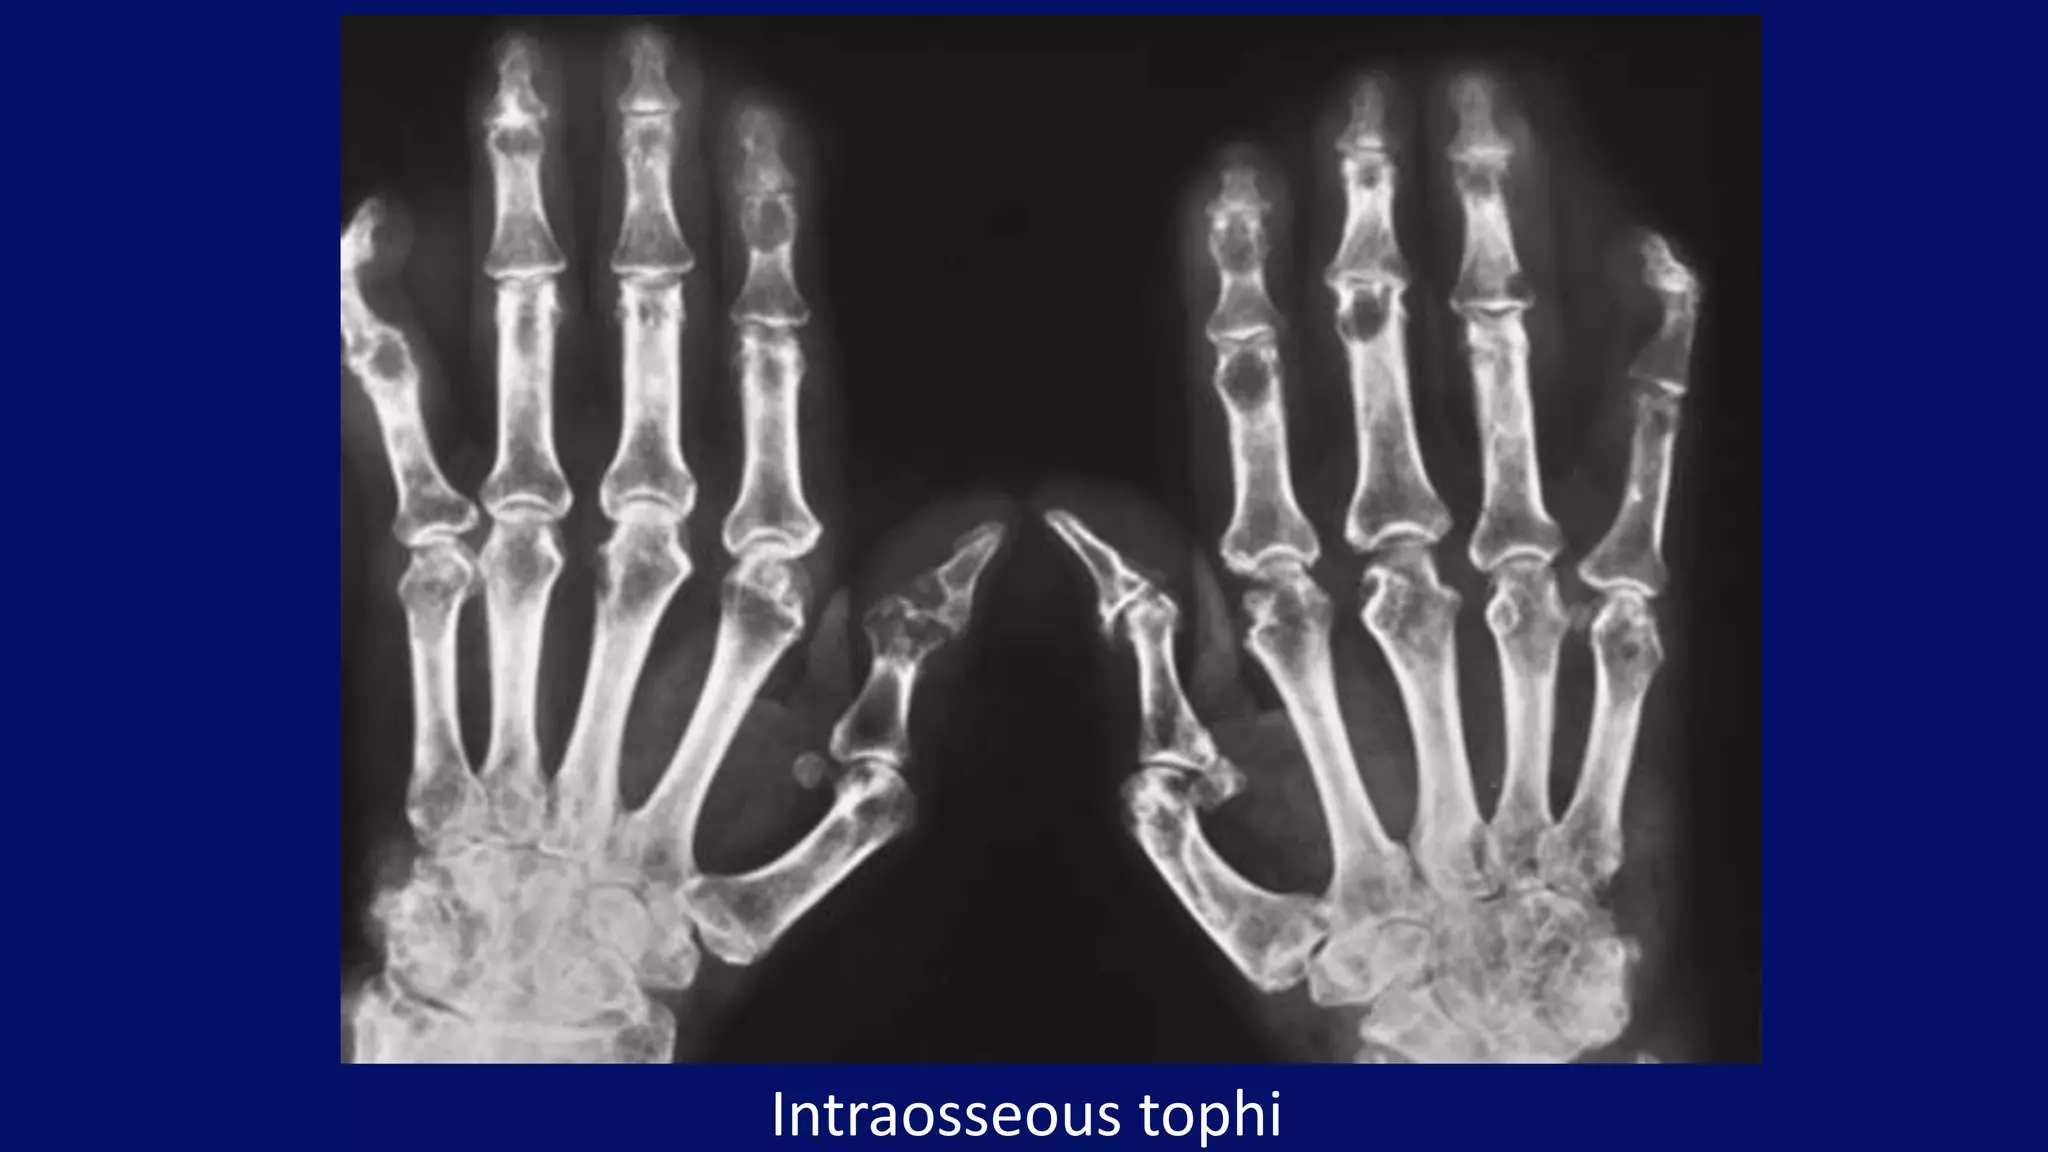

Intraosseous tophi

• #127 Dorsovolar radiograph of both hands of a 60-year-old man with gout shows articular and periarticular erosions. In addition, note the presence of intraosseous defects in the phalanges consistent with intraosseous tophi.